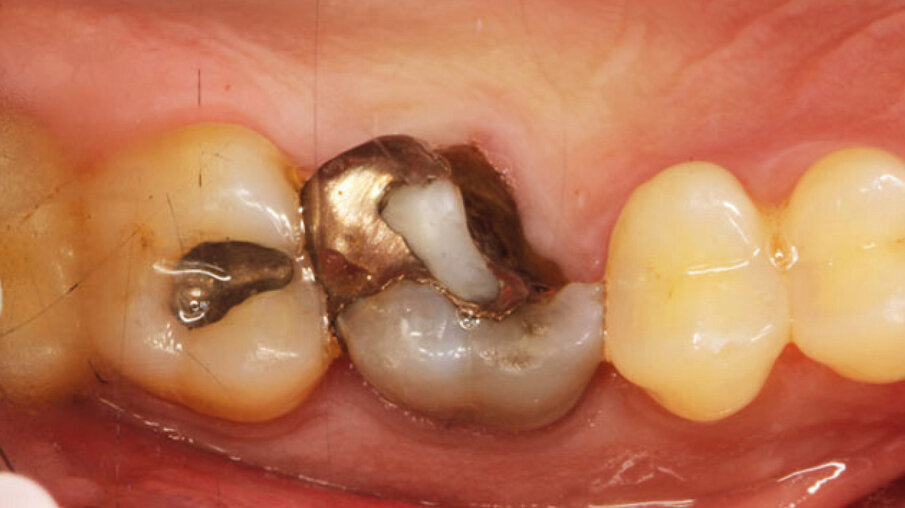

Un paziente maschio (ASA I), senza patologie croniche sistemiche e non fumatore, è stato sottoposto all’estrazione dell’elemento 16 a seguito del fallimento di terapie endodontiche e dell’impossibilità di eseguire un restauro coronale (Figg. 1a, 1b). Nella selezione del paziente sono stati criteri di esclusione: pregressa radioterapia nel distretto testa/collo, assunzione di farmaci che possano indurre ONJ, disordini ematici coagulativi, bruxismo, scarsa igiene orale domiciliare, occlusione instabile, carie non trattate, malattia parodontale non controllata, denti adiacenti a quelli da estrarre con mobilità di grado I o superiore, aspettative di risultato irreali, impossibilità o non propensi a tornare ai controlli di routine e di follow-up. La situazione dei tessuti è stata valutata pre-operatoriamente tramite radiografia periapicala (Fig. 1c) (VistaScan Mini Plus, Dürr Dental). Tramite la CBCT pre-operatoria è stato possibile fare una programmazione implantare. Sulla base dell’anatomia coronale è stata definita la posizione implantare (OnDemand3D, Cybermed), da questa analisi sono stati decisi anche il diametro e la lunghezza dell’impianto.

Fig. 1a - Foto iniziale occlusale.

Fig. 1b - Foto iniziale vestibolare.